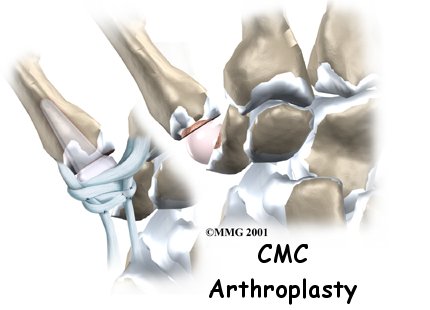

If nonsurgical treatments are not successful in easing problems of thumb arthritis, your doctor may recommend replacing the surfaces of the joint. Joint replacement surgery is called arthroplasty.

Surgeons have several ways to replace the thumb joint surfaces. One way is to attach the ends of a prosthesis implant into the bones of the thumb joint. A newer method uses a small, marble-shaped implant to form the new joint surfaces. This spherical implant works like a ball bearing to give the joint a smooth arc of movement.

A burr (a small cutting tool) is used to make a canal into the bones that form the thumb joint. The surgeon sizes the stem of the prosthesis to ensure a snug fit into the canal and inserts it. When the new joint is in place, the surgeon wraps the joint with a strip of nearby tendon. This gives the new implant some added protection and stability.